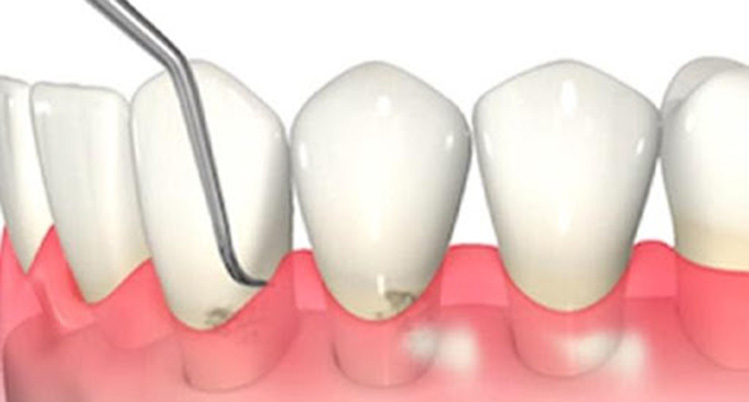

2. スケーリング(歯石除去)

歯科医院で行うクリーニングの中に含まれるもので、専用の機械や器具を使用して歯石を取り除きます。

歯石の表面にはざらつきがあり、プラークが溜まりやすくなるため定期的に除去しましょう。

超音波の振動で汚れを落とすイメージ写真